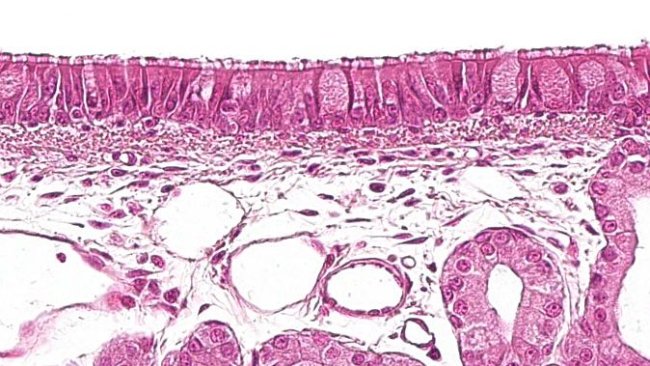

猪肺炎支原体与猪呼吸系统的大多数混合感染有关。它是如何起作用的,有什么影响?

猪的呼吸防御系统由哪些细胞构成?他们组织结构如何,又是怎么相互传递信息的?